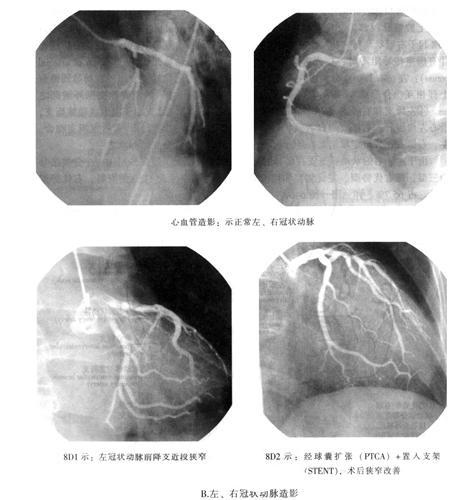

营养心壁的动脉有左、右冠状动脉,都是主动脉起始部的分支(图6-2A~D,图6-8A、B)。

图6-8 心脏的动脉(A、B)

图6-9 左、右冠状动脉(A)

图6-9 左、右冠状动脉(B)

由于左、右冠状动脉分支在膈面的分布范围变异较大,现按Schlesinger分类法分为三型,即右优势型、左优势型和均衡(势)型。据中国人1150例资料,右优势型多见,占65.7%。详见图(图6-9A)。

据临床观察:心肌梗死左冠状动脉比右冠状动脉较为常见。故心肌梗死多发生于左心室的一定范围,其中左心室前壁、心尖部及室间前2/3,约占全部心肌梗死的50%,这些区域正是左冠状动脉前降支血供的解剖部位(图6-9A、B)。不难理解心肌梗死的解剖位置与闭塞的冠状动脉血供范围相一致。基于冠状动脉分布变异较大,故熟悉冠状动脉分布的相关变异,有临床参考意义。